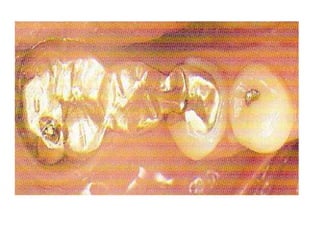

Types of crowns:

*full veneer metal

crown: it is a full

metal cast crown

that covers all the

coronal tooth

surface.

2-According to material used:

1- Metallic:

A- high noble alloy

B- noble alloy

C- predominantly base metal.